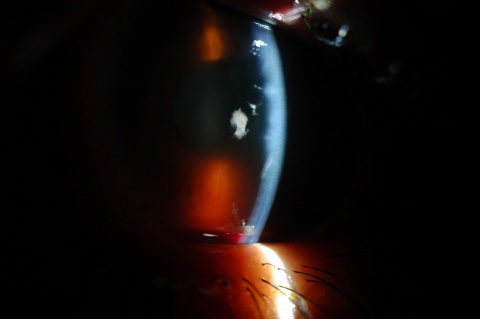

Signs

A large hyphema can be noted with pen-light examination alone. The height and color of the hyphema should be documented. Height can be measured in millimeters from the inferior corneal limbus. Color can vary from red to black depending on the time frame of the hyphema. Blood that has clotted will appear darker in appearance (black). It is important to evaluate intraocular pressure.

- Grade IV: There is total filling of the anterior chamber with blood. If the anterior chamber is completely filled with bright red blood, it is called a total hyphema. If the anterior chamber is filled with dark red-black blood, it is called a blackball or 8-ball hyphema. The black color is suggestive of impaired aqueous circulation and decreased oxygen concentration. This distinction is important because an 8-ball hyphema is more likely to cause pupillary block and secondary angle closure.[6]